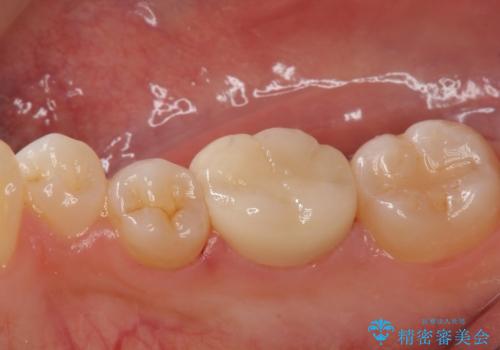

- 仮歯・ジルコニアクラウン 12.1万円費用は治療当時の料金となります

多少大きく削ることになりましたが希望に沿った処置となり、満足して頂けました。